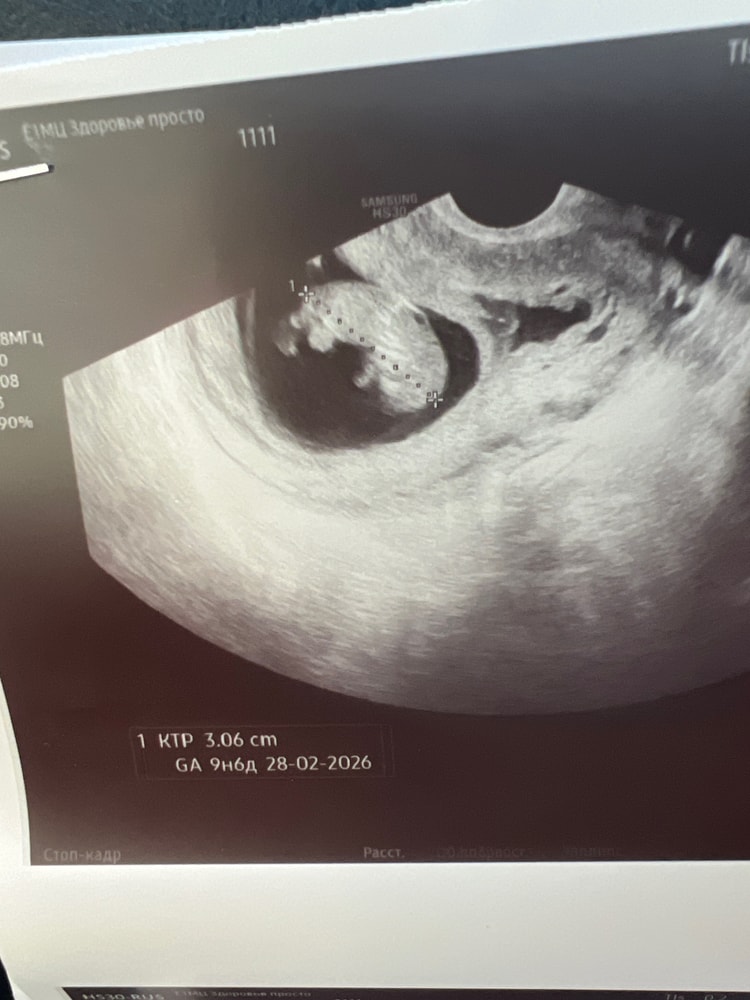

Привет, девчонки! Давно не писала. Сходила сегодня на узи только ради НИПТ, который завтра буду сдавать.

Малыш очень активен) пока смотрели, он весь истанцевался) ручки, ножки как у полноценного человека. Виднелись косточки. Вроде как даже пипирку было видно, но врач сказала что это может быть и пуповина, чтобы я сильно не надеялась) КТР 3,11. Растем, развиваемся, все у нас хорошо)

😃Сегодня сдала НИПТ. 🤞🏻скрестила пальцы за себя и Вас. У меня по М сегодня 10+1, по КТР вчера поставили 11н.